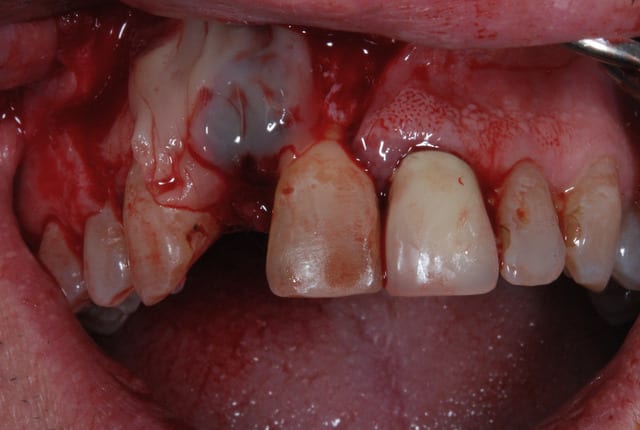

Vous tenteriez l'EII dans ce cas ci

Il y a 3.6 mm d'os au dessus du granulome

si tu veux aller au casse pipe....

pas que pour le granulome...d'ailleurs...mais aussi parce que tu as une belle fracture vestibulaire qui fait que la corticale...bein y en a plus...ou quasi plus...

la seule condition pour tenter: faire une box technique au sonicweld...et encore, autant dans un secteur pas trop esthétique, je dis pas...mais là...si çà foire c'est le drame...

les 2 cas ne me semblent pas comparable dans la mesure ou tu as réussi à préserver un bandeau d'os vestibulaire presque au niveau des collets. Il permet un effet piquet de tente incomparable et évite les mauvaises surprises de perte importante de volume de biomat a la cicatrisation.

Dans l'autre cas la table vestibulaire est manquante, le résultat d'une EII beaucoup moins prévisible et dans un secteur esthétique j'aime pas jouer a la roulette russe.